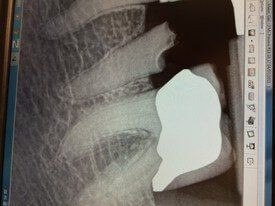

- It acts as an artificial root, usually made of titanium, that is surgically placed into the jawbone to replace the root of the natural tooth.

An immediate dental implant, or Teeth in a Day®, is placed in the jawbone immediately after a single tooth (or teeth) extraction. It is usually placed in the same visit as the extraction but can be done after two weeks and still qualify as an immediate dental implant.